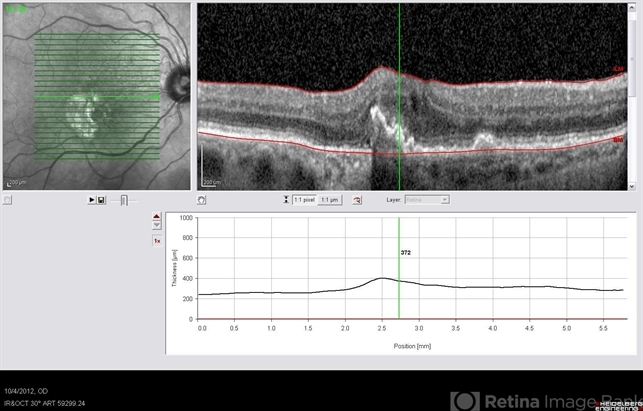

- retinal pigment epithelium, optical coherence tomography (OCT)

- Imaging device

- Scanning laser ophthalmoscope